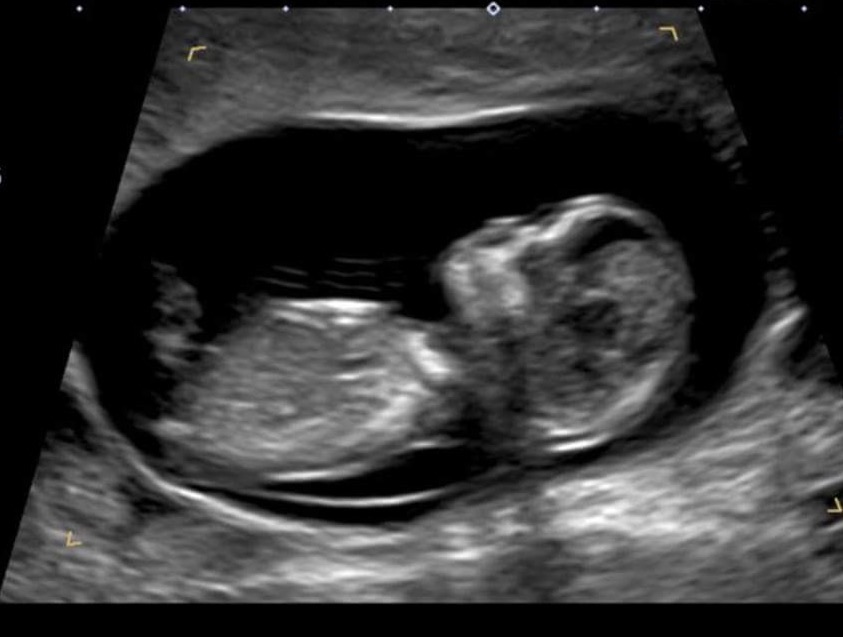

Any guesses whether it's a boy or girl. At 12W 4D.Attachment 33296

Very difficult pic, could be boy, but really it's still more like 50/50.